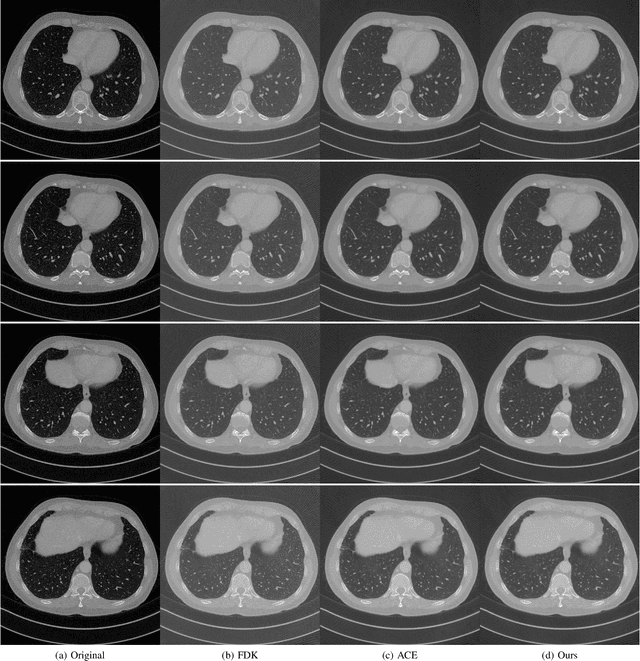

Abstract:In this paper, we propose a new GPU implementation of the Katsevich algorithm for helical CT reconstruction. Our implementation divides the sinograms and reconstructs the CT images pitch by pitch. By utilizing the periodic properties of the parameters of the Katsevich algorithm, our method only needs to calculate these parameters once for all the pitches and so has lower GPU-memory burdens and is very suitable for deep learning. By embedding our implementation into the network, we propose an end-to-end deep network for the high pitch helical CT reconstruction with sparse detectors. Since our network utilizes the features extracted from both sinograms and CT images, it can simultaneously reduce the streak artifacts caused by the sparsity of sinograms and preserve fine details in the CT images. Experiments show that our network outperforms the related methods both in subjective and objective evaluations.